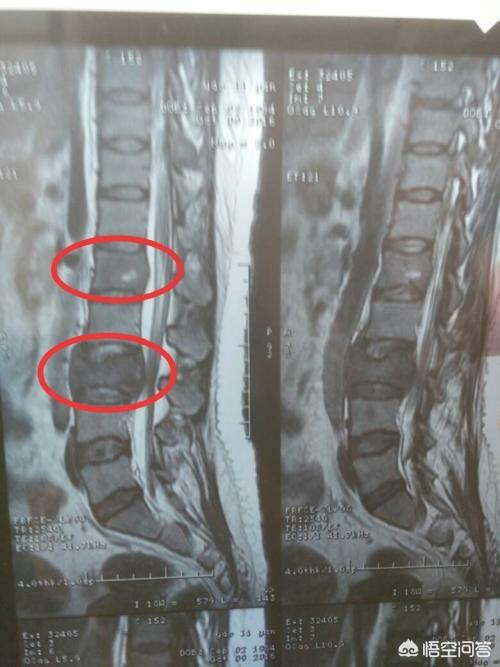

骨転移はどのような痛みに注意すべきですか?骨転移は悪性腫瘍の末期によく見られる症状で、体の他の部位にある原発腫瘍が血液やリンパ液の経路を通って骨に転移し、骨転移を形成することを指します。骨転移は、正常な骨組織が破壊され、腫瘍組織に置き換わっていることを示す。骨転移は病変の特異性により、溶骨型、造骨型、混合型の3つに分類される。骨転移の好発部位は中軸骨(脊椎、骨盤)、肋骨、下部骨幹部で、特に中軸骨が最も多く、これはこの部位の血液供給の特徴と関係しています。下の円のように骨転移が多発し、脊椎の状態が悪い。

骨転移で起こる症状にはどのようなものがありますか?最初の症状は痛みです。骨転移を起こした部位は骨が破壊されるために痛みを感じますが、最初ははっきりした症状がなかったり、断続的な痛みだったりしますが、腫瘍が正常な骨をどんどん破壊して徐々に悪くなっていくため、転移部位の痛みも徐々に悪くなっていきます。臨床的には、体のある部分の骨の痛みで、悪性腫瘍の骨転移という症例に出くわすことがあります。以前、ある症例に出会ったのですが、40歳で、肩が痛く、五十肩かと思い、薬用オイルを数日揉んでも改善が見られず、ますます痛みが強くなったので、病院で検査をしたところ、MRIを撮ったところ、肩甲骨が(腫瘍の)かけらに食べられており、骨転移を考え、胸部CTを撮ったところ、右肺に結節があり、生検をして病理検査をしたところ、肺がんの骨転移でした。その内容は以下の通りである。

骨転移部位では、正常な骨組織が破壊され腫瘍組織に置き換わり、腫瘍細胞は常に増殖しているため、多くの骨転移部位で軟部組織の腫瘤影が見られ、腫瘤が表在する部位であれば触知することができる。また、腫瘍組織による正常な骨組織の侵食は、正常な骨構造の破壊と脆弱化につながるため、正常な外力下でも骨折が生じることがあり、病的骨折と呼ばれます(下図)。脊椎への転移は、疼痛や病的骨折に加えて、脊髄神経根の圧迫を伴い、感覚障害、筋力低下、場合によっては高カルシウム血症などの症状を呈することもあります。

胸椎に発生した骨転移性癌を示す。